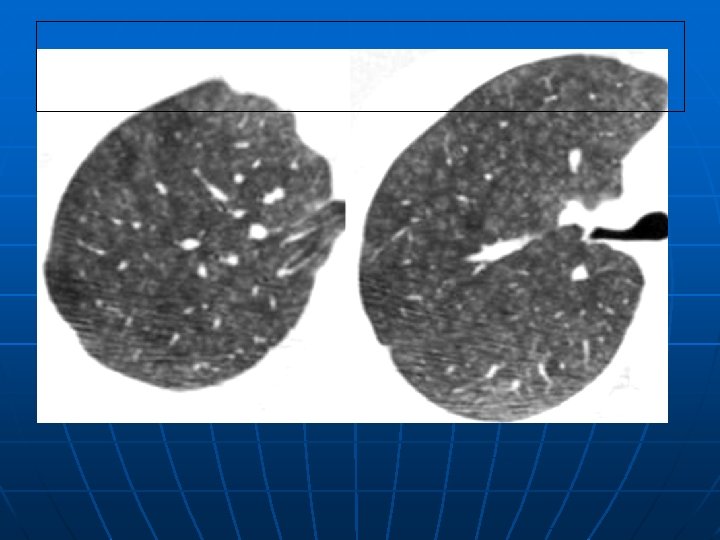

It's called Head cheese because a lot of the meat in it comes from the head, like the cheek, tongue, some use lips, ears, and any left over meat scraps from trimming other cuts of meat from the carcass That being said, it is not an organ meat loaThis pattern of mixed parenchymal lung densities has been likened to the morphologic appearance of the mixture of boiled pork scraps and pigs' feet in a gelatinous background known and marketed as head cheese or hog's head cheese and is therefore known as the "head cheese sign" or "hog's head cheese sign" 25, 26 How does this particular imaging sign help radiologists in theirHeadcheese Sign Chong, Bradford J BS;

Jun 01, 17 · Head Cheese Sign Head cheese is a type of terrine made from pieces of meat obtained from various parts of different animals, such as a calf or pig ( Fig 15 A ) The head cheese sign is characterized by the juxtaposition of distinct radiographic areas of low, normal, and high attenuation 38 The CT scan image bears close resemblance to the cut surface of a head cheeseHead Cheese and Pate The Polish deli is not only known for its sausages and excellent array of cold cuts It is also recognized for its more unique products such as head cheeses and pâtés, or "salceson" and "pasztet," respectively, in PolishIn southern Louisiana, hog's head cheese is a specialty that used to be a deli and butcher shop staple A glistening block of quivering meat, this "cheese" is dairyfree, but emphatically

Keywords "head cheese sign", "hilum convergence sign", "hilum overlay sign", "hogs head cheese sign", "incomplete border sign", luftsichel sign, thoracic imaging, "walking man sign", "water bottle sign"Game Time Football TShirt 50 out of 5 stars 1Hog's Head Cheese Sign A term of art referring to a CT appearance in which there are mixed densities of lung parenchyma which has been fancifully likened to the appearance of the mixture of boiled pork scraps and pigs' feet in a gelatinous base which is marketed as hog's head cheese The hog's head cheese pattern indicates a mixed infiltrative pattern characterized by groundglass

Hog's Head Cheese Sign A term of art referring to a CT appearance in which there are mixed densities of lung parenchyma which has been fancifully likened to the appearance of the mixture of boiled pork scraps and pigs' feet in a gelatinous base which is marketed as hog's head cheese The hog's head cheese pattern indicates a mixed infiltrative pattern characterized by groundglass orHead Cheese Carefully crafted with select cuts of ham blended with sweet red peppers, this Old World terrine resembles a rough pâté and is uncommonly flavorful Boar ' s Head Head Cheese is an authentic take on a traditional German delicacy Gluten FreeKanne, Jeffrey P MD;